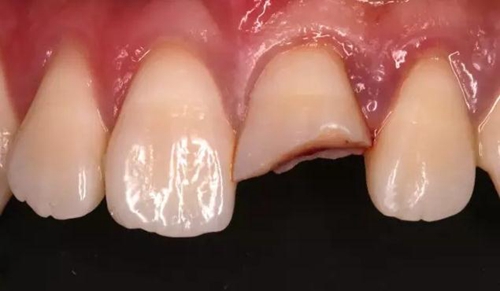

術(shù)前口內(nèi)照

斷冠

折斷之牙體嚴(yán)重脫水,呈白堊色,斷端對(duì)位后吻合度較好,僅少許牙體缺損。

斷冠粘接前試對(duì)接